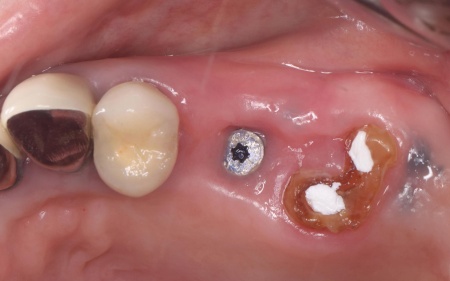

| 行ったご提案・治療内容 | 患者様には、折れた左上奥歯は温存ができず、歯根を抜く必要があることをお伝えしました。 そのうえで、希望されているインプラント治療を行うために必要な点を説明しています。 ・インプラント治療に必要な骨の量を確保するための「骨補填」を行う こちらに同意いただき、3ヶ月後からインプラント治療を始めることになりました。 まず、左上奥歯を抜きます。 3ヶ月後、顎の骨の状態が良好であることを確認し、インプラントを埋入する手術を実施しました。 |

治療後